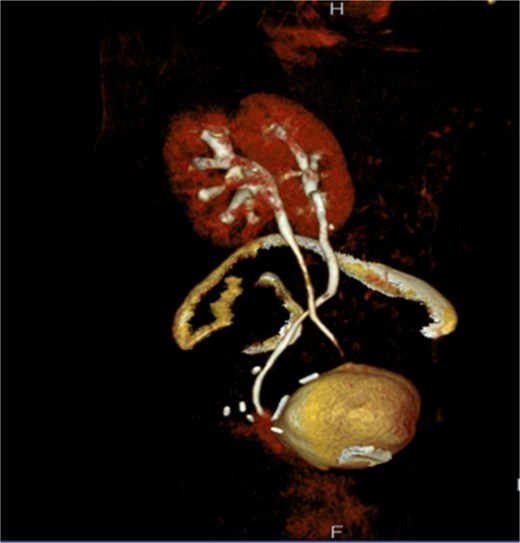

Intraoperatively, fibrotic adhesions were found and the lower part of right ureter was found clamped with the vaginal stump and bladder and an ureterocystotomy with antireflux ureter reimplantation were performed. Detachment of the ureter from the vagina was performed, using part of the peritoneum to seal the detached area, in order to prevent further fistula formation and the bladder wall was closed in two layers and a transurethral catheter was placed (Fig. 3).

The 3D image of reimplantation of the right ureter with antireflux technique in the dome of the bladder.